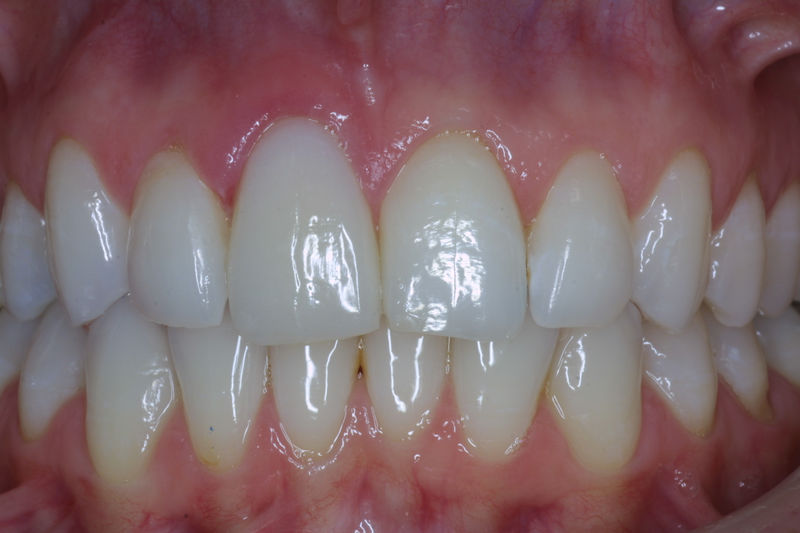

Amplia gama de tratamientos para mejorar la apariencia de la sonrisa, corrigiendo el color, la forma, el tamaño, la alineación y la posición de los dientes. Los procedimientos más comunes y solicitados incluyen el blanqueamiento dental, las carillas y coronas, así como las resinas.

Son restauraciones que cubren toda la cara frontal del diente, generalmente empleadas en el sector anterior y cuya finalidad es primariamente estética.

Restauraciones fabricadas en el laboratorio con materiales estéticos, los cuales cubren de manera total dientes anteriores y posteriores. Se utilizan primariamente para restaurar dientes con caries, fracturas y/o defectos amplios, así como soportes de puentes. Para poder enviar el caso al laboratorio se toman impresiones utilizando materiales de impresión o técnicas modernas digitales.